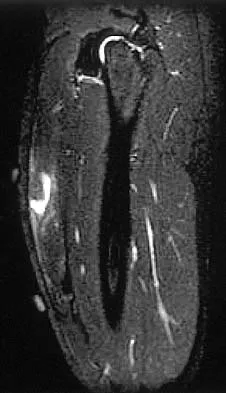

Figure 42 shows the sagittal T2-weighted MRI scan of a patient's right knee. These findings are most commonly seen with a complete tear of the

The MRI scan reveals disruption of the lateral capsule and ligaments with fluid in the soft tissues laterally. Additionally, there is a large bone bruise on the medial femoral condyle. This combination indicates injury to the posterolateral complex. These injuries often have coexisting anterior and/or posterior cruciate ligament injuries. Failure to recognize the posterolateral corner injury can lead to failure of anterior or posterior cruciate ligament reconstructions. LaPrade RF, Gilbert TJ, Bollom TS, et al: The magnetic resonance imaging appearance of individual structures of the posterolateral knee: A prospective study of normal knees and knees with surgically verified grade III injuries. Am J Sports Med 2000;28:191-199.